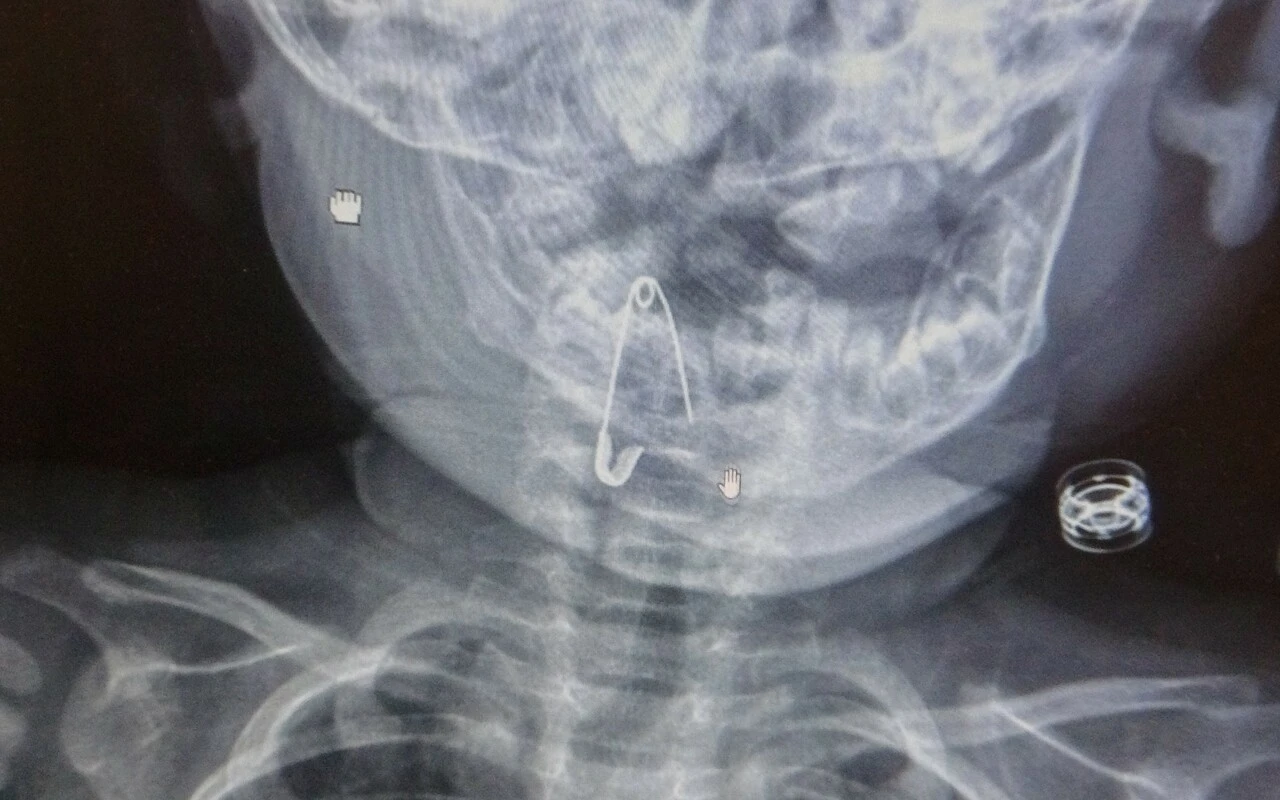

Bitlis’in Güroymak ilçesinde, soluk borusuna çengelli iğne kaçan 8 aylık bebek, yapılan başarılı bir operasyonla sağlığına kavuştu.

Güroymak ilçesinde 8 aylık bebek, evde bulunan çengelli iğneyle oynarken onu yuttu. Öksürmeye başlayan minik çocuğun, hastanede çekilen röntgen sonucu çengelli iğneyi yuttuğu fark edildi. Güroymak Devlet Hastanesi’nden Tatvan Devlet Hastanesi’ne ambulansla sevki gerçekleşen minik çocuk, Kulak Burun Boğaz Hastalıkları Uzmanı Operatör Dr. Hakan Tuhan tarafından yapılan başarılı operasyonla sağlığına kavuştu. Çengelli iğnenin saplı olduğu soluk borusundan çıkarılan bebek, 2 saatlik gözlemin ardından taburcu edildi.

Konuyla ilgili açıklamada bulunan Kulak Burun Boğaz Hastalıkları Uzmanı Operatör Dr. Hakan Tuhan, “8 aylık bir bebek, Bitlis’in Güroymak ilçesinden tarafımıza danışıldı. Güroymak ilçesinde çekilen röntgen sonucunda çengelli iğnenin soluk borusunun girişinde olduğunu teyit ettik. Yapılan müdahaleler sonucunda çengelli iğneyi çıkardık. Çıkardıktan sonra iki saat kadar gözlem altında tuttuk hastamızı. Daha sonrasında herhangi bir komplikasyonla karşılaşmadık ve sorunsuz bir şekilde taburcu ettik” dedi.